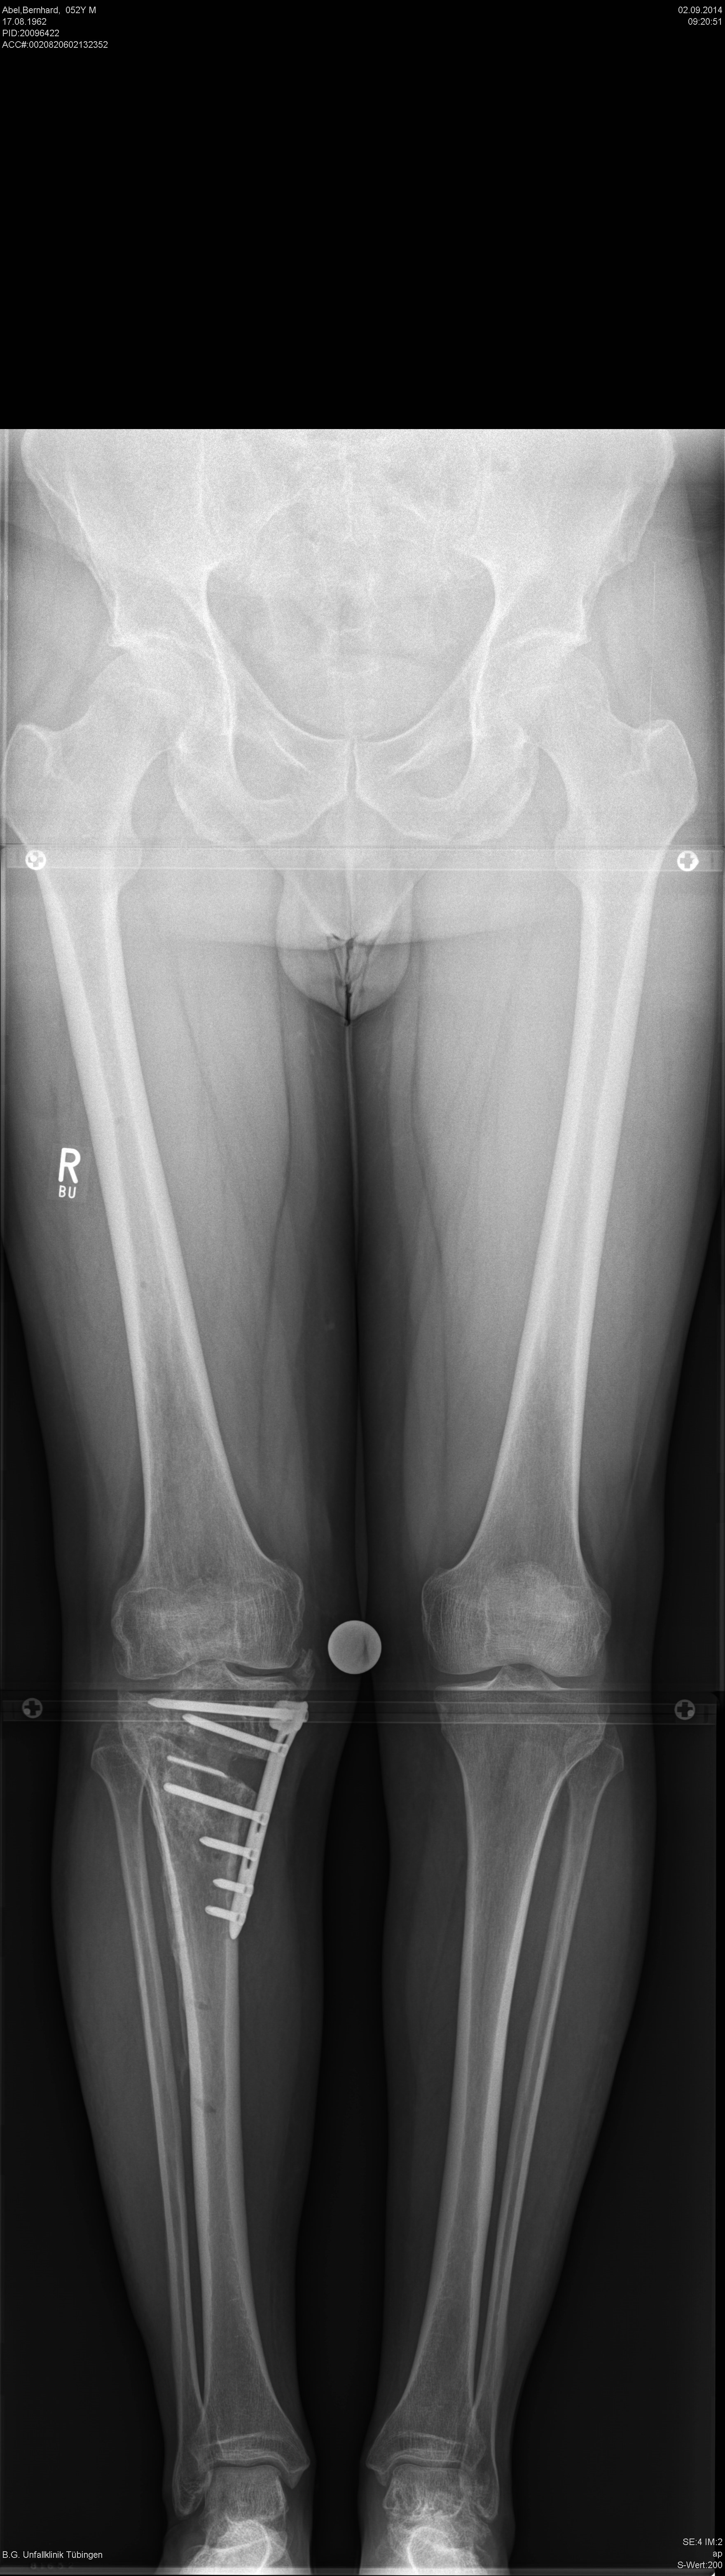

A 33-year-old woman complained of pain in the lateral compartment after a normal working day. Sports activities were no longer possible. Free range of motion (ROM: 0/0/150°), ligaments in sagittal, and coronal planes were stable. There was no effusion. The patient had valgus deformity which was corrected with a distal femoral osteotomy.

Showcasing a distal femur osteotomy case